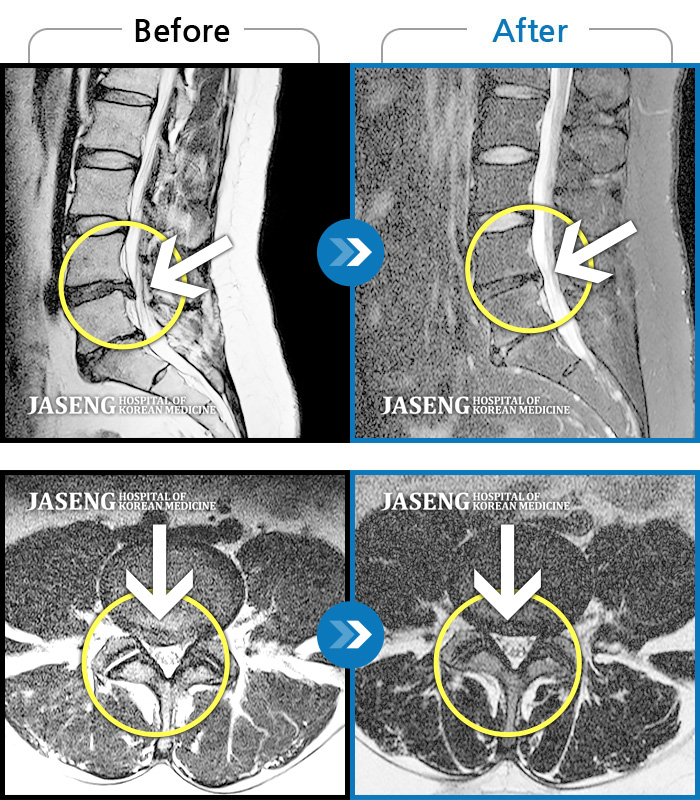

허리디스크

인천 · 강아현 원장

우측 허리 통증 및 다리 저림이 심하여 앉거나 바로 눕는 것도 힘든 상태로 내원하셨습니다. 감각 저하도 동반되어 심각한 신경손상이 의심되는 상황이었습니다.

촬영시기

2024.07.27 ~ 2025.04.05

2025.04.16

조회수 350